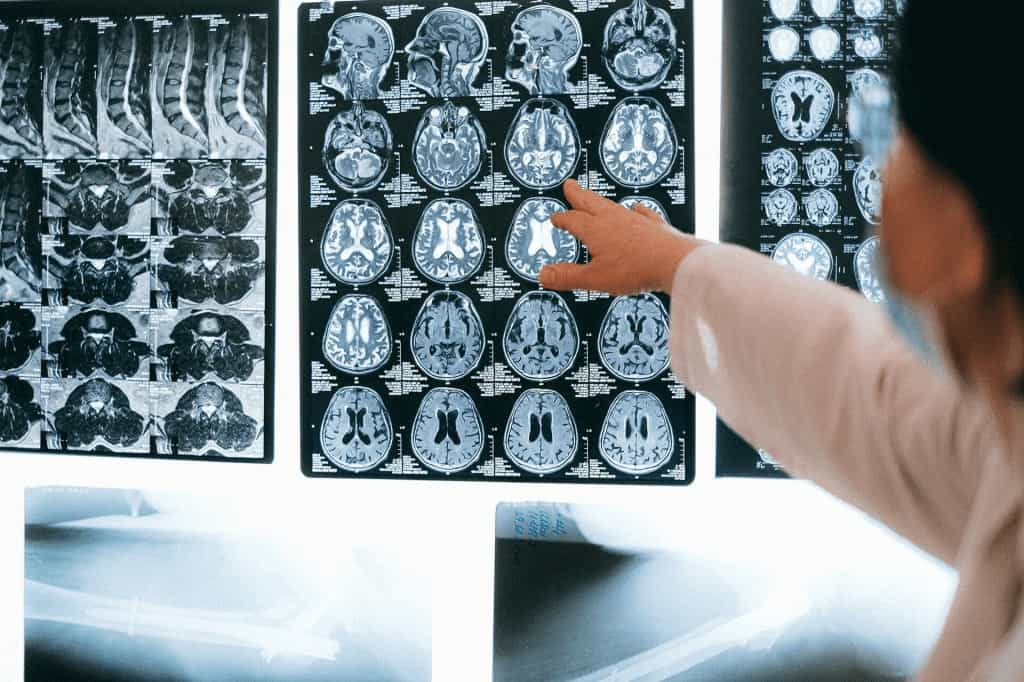

Beyin hasarı ilk aşamada bilgisayarlı tomografi (BT) ile görüntülenir. Beyin içi kanama, ödem, fıtıklaşma gibi ölümcül olabilecek sorunların belirtileri yönünden BT incelenir.